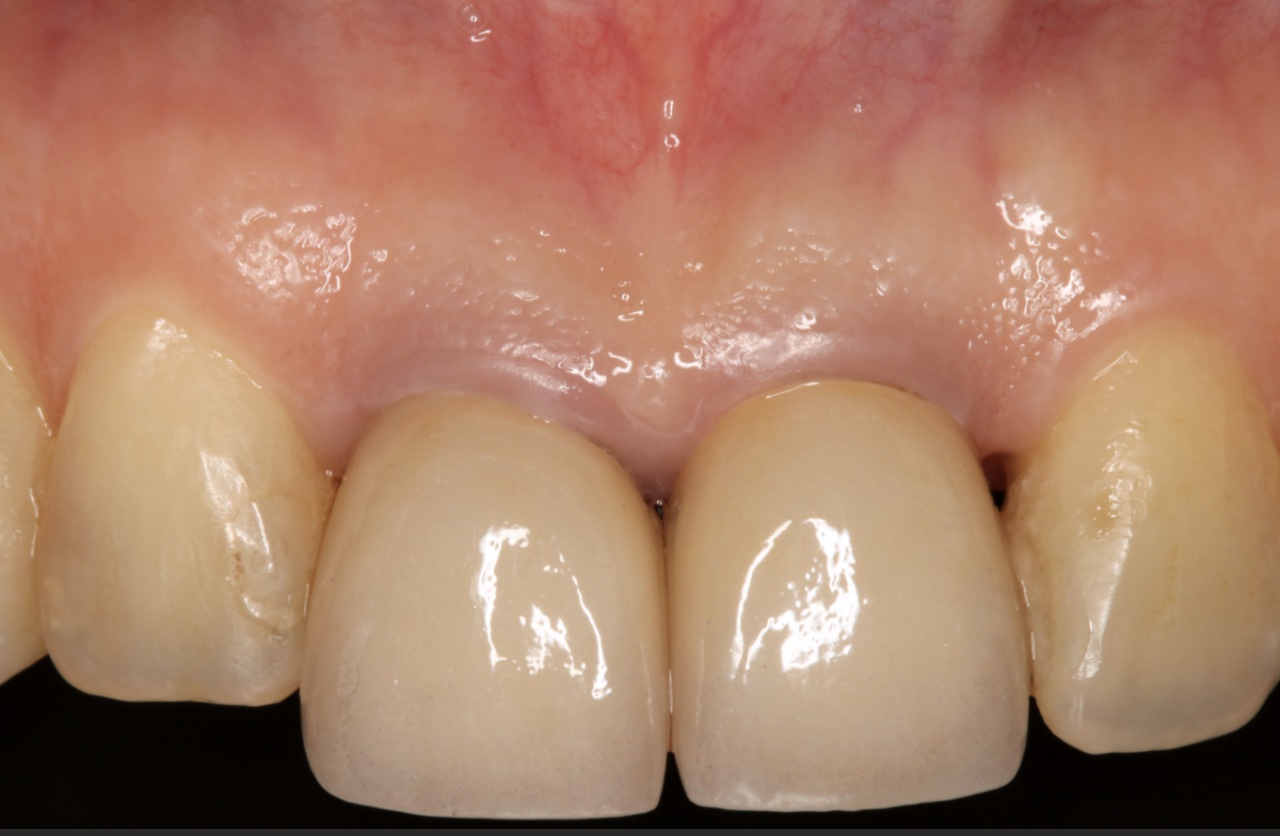

長期追蹤觀察:增加植體角化上皮 Long-term Follow Up of Increase Keratinized Mucosa Around Implant

因為幫學會上課,藉由這次機會,整理了五個長期案例,至少八年到十二年的追蹤。觀察照片,移植角化上皮,經過長年觀察,粗略估計,一年後就很穩定,且多年後,萎縮量沒有很多,蠻平穩的。

以前台大老師有提過,時間久了,可能會因為肌肉層附連拉扯,即使補的寬度多很多,前後MGJ的連線還是會呈現一直線,原有多補的會縮一些回去。不過,我自己的案例,例如Case D,經過九年後,角化上皮還是很寬,呈現前後連線不是很一致的狀態。有這些發現,其實蠻有意思的~